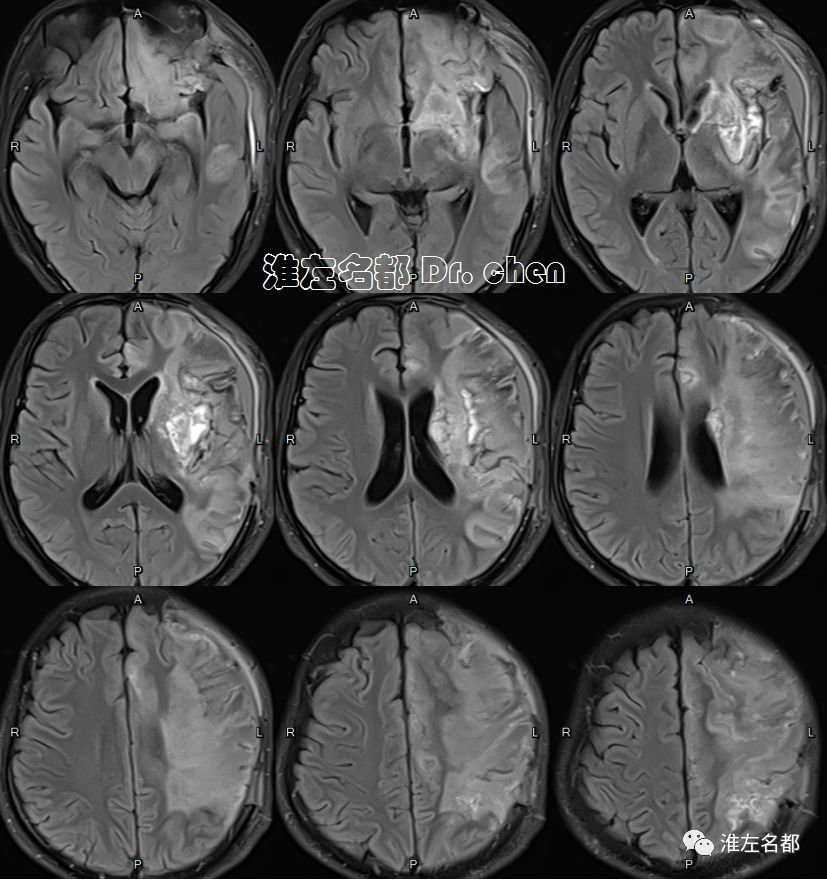

MRI

2019-9-19

△T2WI、T1WI、FLAIR和SWI:左侧半球大面积亚急性梗死伴渗血,局部软化坏死。

△3D-TOF-MRA:左侧大脑中动脉M1段和前动脉A1段管腔显影不规则;左侧大脑中动脉分支显影较对侧稀疏(考虑和大面积梗死后供血需求降低有关)。